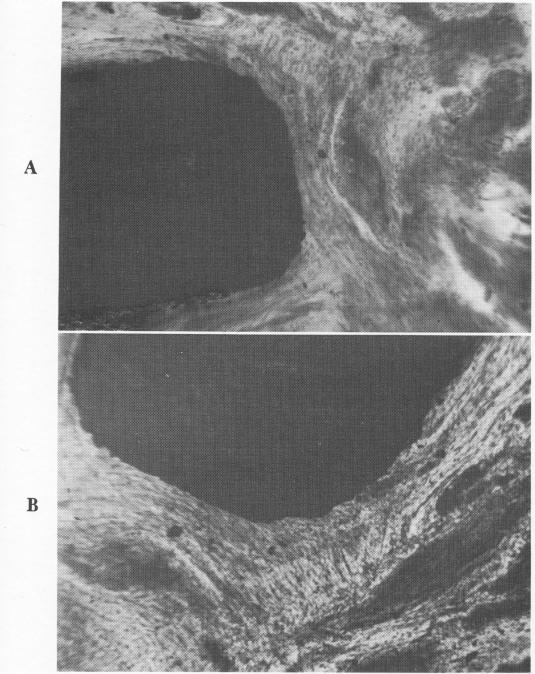

Fig. 4-95. A, Under low power the soft tissues were clearly oriented around the tantalum subperiosteal implant post. B, Although the soft tissue elements in this slide are more loosely organized, they are still oriented around the post site. (Courtesy L. Marziani.)

Professor Luigi Marziani of Rome carefully re-moved the tissues around tantalum subperiosteal implant posts and prepared slides to determine their organization. Some were more loosely organized than